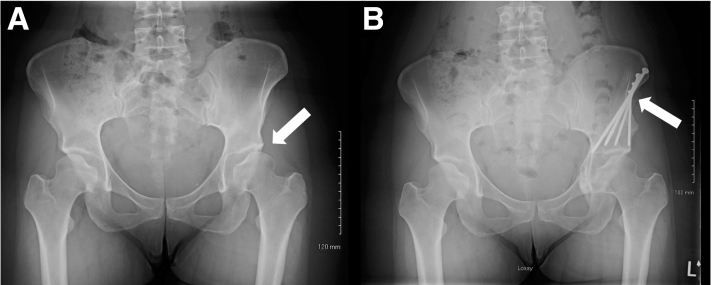

Fig 7.

Side-by-side (A) pre- and (B) postoperative standing anteroposterior pelvis radiograph with (A) the affected left hip and (B) periacetabular osteotomy screws marked by an arrow.